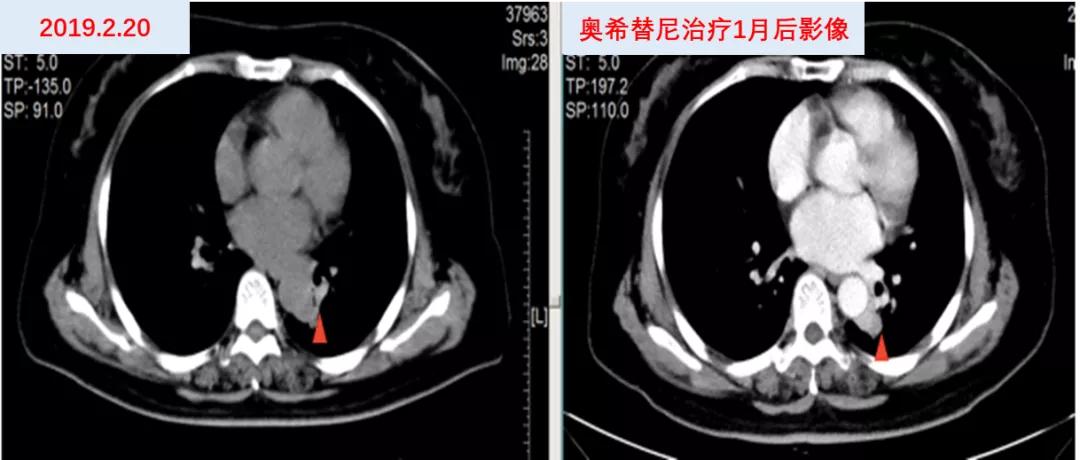

2019年2月26日因“活动后气促”于福建省东山县医院查胸部CTA示:左肺癌及化疗后改变,双肺下叶少许炎性灶,纵隔内及双肺门淋巴结肿大,肝内低密度灶,考虑转移灶?左右肺动脉局部及其部分分支充盈缺损,考虑癌栓形成。分子病理(ctDNA,ddPCR)EGFR T790M 0.89%。2019年2月28日开始口服“奥希替尼80mg qd”靶向治疗,并予低分子肝素抗凝治疗。2019年3月26日复查提示肺动脉瘤栓较前好转,左肺病灶较前略增大。(图6)

因考虑左肺病灶较前略增大,患者继续口服“奥希替尼80mg qd”靶向治疗,并于2019年3月26日开始联合“长春瑞滨40mg d1,3,5(口服3周停1周)”节拍化疗,定期复查疗效评价SD,PFS接近12个月。(图7)

图6 奥希替尼治疗前后影像资料

图7 “奥希替尼+长春瑞滨”治疗前后影像资料